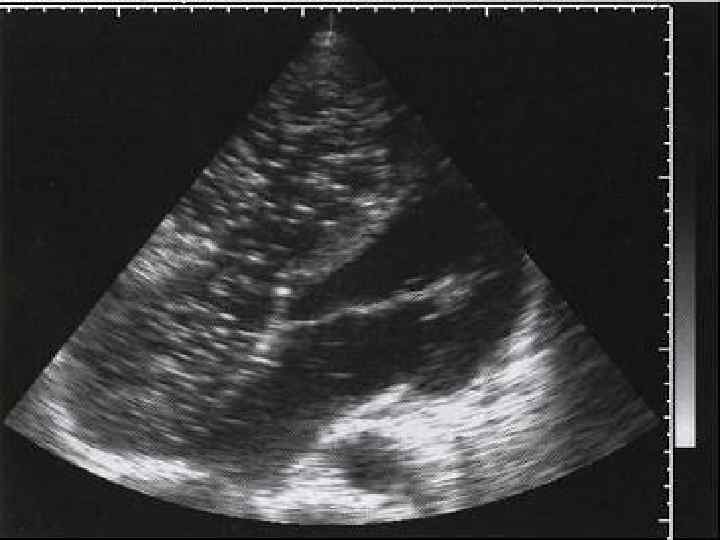

ОЦЕНКА НАРУШЕНИЙ РЕГИОНАЛЬНОЙ СОКРАТИМОСТИ ЛЕВОГО ЖЕЛУДОЧКА Выявление локальных нарушений сократимости ЛЖ с помощью двухмерной эхокардиографии имеет важное значение для диагностики ИБС. Исследование обычно проводится из верхушечного доступа по длинной оси в проекции двух и четырехкамерного сердца, а также из ле вого парастернального доступа подлинной и короткой осям. В соответствии с рекомендациями Американской ассоциации эхокардиографии ЛЖ при этом условно делится на 16 сегментов, располагающихся в плоскости трех поперечных сечений сердца, зарегистрированных из левого парастернального доступа по короткой оси. Изображение 6 ти базальных сегментов — переднего (А), переднеперегородочного (AS), задне перегородочного (IS), заднего (I), заднебокового (IL) и переднебокового (AL), — получают при локации на уровне створок митрального клапана (SAX MV), а средних частей тех же 6 ти сегмен тов — на уровне тапиллярных мышц (SAX PL). Изображения 4 верхушечных сегментов перед него (А), перегородочного (S), заднего (I) и бокового (L), — получают при локации из парастер нальногодоступа на уровне верхушки сердца (SAX АР).

Локальная сократимость ЛЖ Нарушения локальной сократимости отдельных сегментов ЛЖ у больных ИБС принято описывать по пятибалльной шкале: 1 балл — нормальная сократимость; 2 балла — умеренная гипокинезия (незначительное снижение амплитуды систолического движения и утолщения в исследуемой области); 3 балла — выраженная гипокинезия; 4 балла — акинезия (отсутствие движения и утолщения миокарда); 5 баллов дискинезия (систолическое движение миокарда исследуемого сегмента проис ходит в направлении, противоположном нормальному). Важное прогностическое значение имеет расчет так называемого индекса локальной сократимости (ИЛС), который представляет собой сумму балльной оценки сократимости каж дого сегмента (2 S), деленную на общее число исследованных сегментов ЛЖ (п):